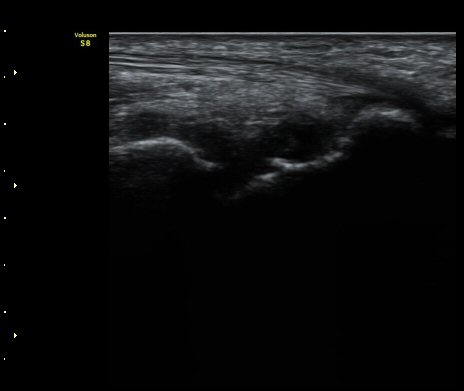

ÃÊÀ½ÆÄ °Ë»ç

ÁÖ»ó°ñ ¼±»ó°ñÀýÀº ´Ü¼ø¹æ»ç¼± ÃÔ¿µ ½Ã È®ÀεÇÁö ¾ÊÀº °æ¿ì°¡ ¸¹Àºµ¥ ÀÌ ¶§ ÃÊÀ½ÆÄ

°Ë»ç°¡ ÁÖ»ó°ñ °ñÀý Áø´Ü¿¡ ¸Å¿ì À¯¿ëÇÏ´Ù. ±×·¯¹Ç·Î ¼Õ¸ñ ´ÙÄ£ ÈÄ Áö¼ÓÀûÀÎ ÅëÁõÀ»

È£¼ÒÇϰí ÁÖ»ó°ñ ºÎÀ§ ¾ÐÅëÀ» º¸ÀÌ´Â °æ¿ì ÃÊÀ½ÆÄ°Ë»ç¸¦ ½ÃÇàÇÏ¿© ÁÖ»ó°ñ °ñÀý ¿©ºÎ¸¦

È®ÀÎÇØ¾ß ÇÑ´Ù.

ÃÊÀ½ÆÄ°Ë»ç¸¦ ½ÃÇàÇÒ ¼ö ¾ø´Â °æ¿ì´Â ÄÄÇ»ÅÍ ÃÔ¿µ°Ë»ç¸¦ ÁÖ»ó°ñ °ñÀýÀ» È®ÁøÇÒ ¼ö ÀÖ´Ù.